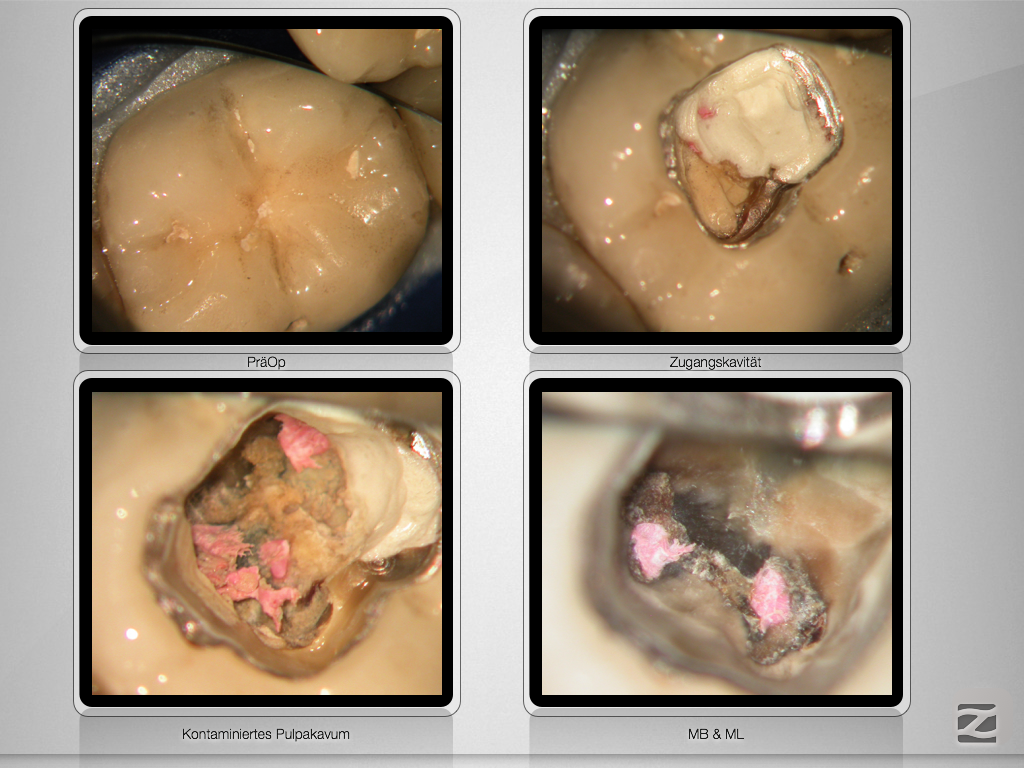

46d-004

Warten auf’s Recall